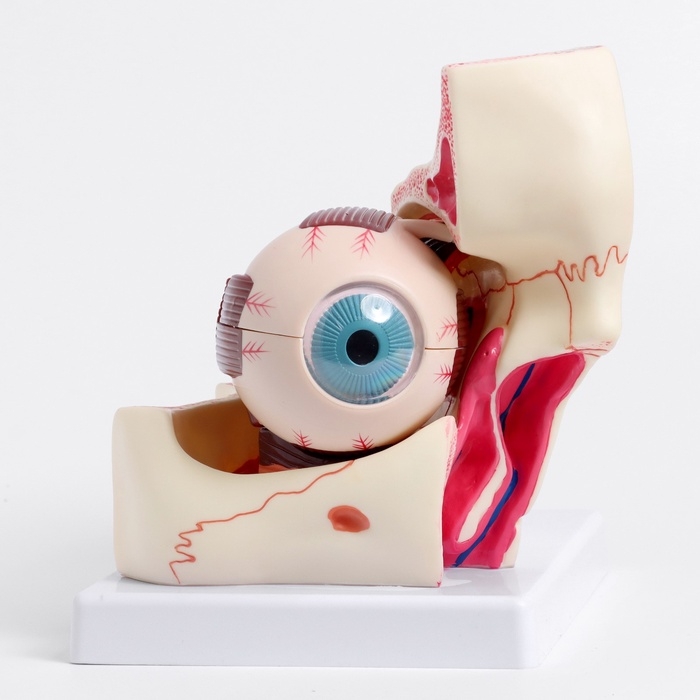

Анатомические модели

ЕКБ 39

No Brand, артикул: 7072361